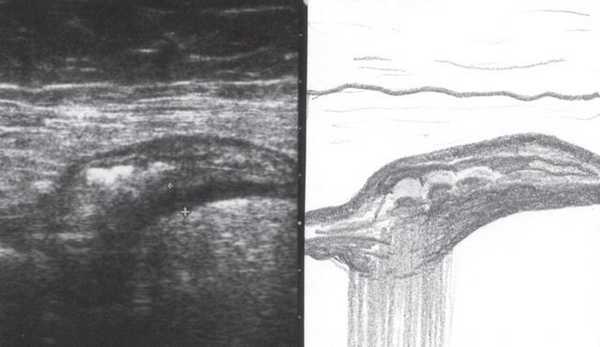

При УЗИ были выявлены диффузные изменения печени и поджелудочной железы, признаки хронического бескаменного холецистита, ангиомиолипома левой почки (без динамики за несколько лет), состояние после экстирпации матки с придатками. В левой подвздошной области соответственно зоне максимальной пальпаторной болезненности на протяжении 9 см отмечалось утолщение стенок толстой кишки до 6-7 мм (рис. 1). Перистальтика кишки отсутствовала, гаустрация была слабо выражена, при этом визуализировалось несколько болезненных при надавливании датчиком выпячиваний пониженной эхогенности, размером от 7 до 20 мм (рис. 2, а, б) с тонкой стенкой до 0,9-1,1 мм и наличием в некоторых из них фрагментов кишечного содержимого и газа (рис. 3, а, б).

Рис. 1. Эхографическая картина дивертикулита. Трансабдоминальное исследование линейным датчиком 7,5 МГц.

"Симптом пораженного полого органа".